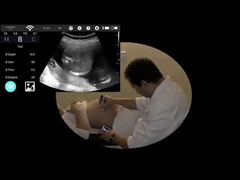

Calidad Escáner de ultrasonido portátil, analizador del ultrasonido del PDA Fabricante de China

Ultrasound scanner